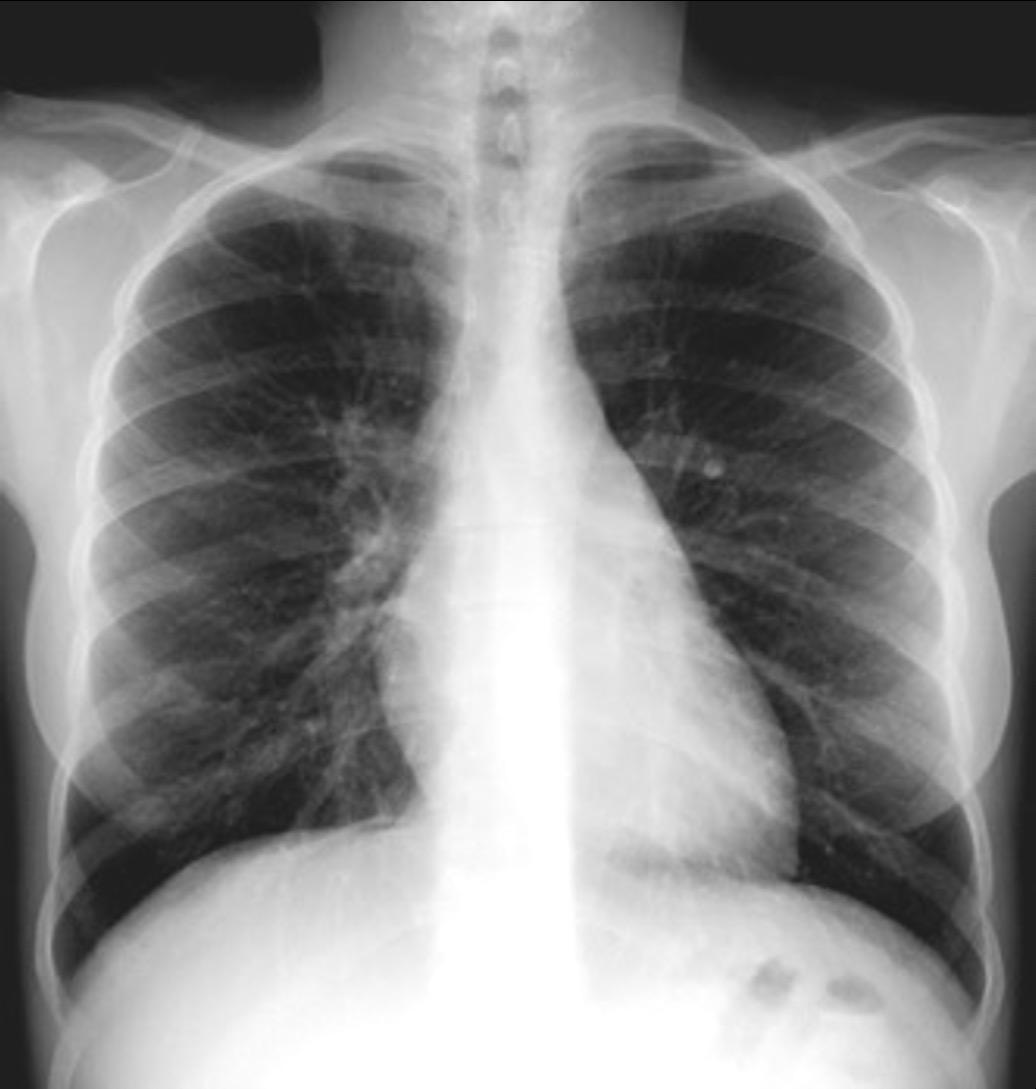

Parálisis frénica transitoria tras cirugía de válvula aórtica

Parálisis frénica transitoria post cirugía cardiaca (10%).

Puede acompañarse de atelectasia del LII.

Benjamin JJ et al. . Left lower lobe atelectasis and consolidation following cardiac surgery: the effect of topical cooling on the phrenic nerve. Radiology 1982